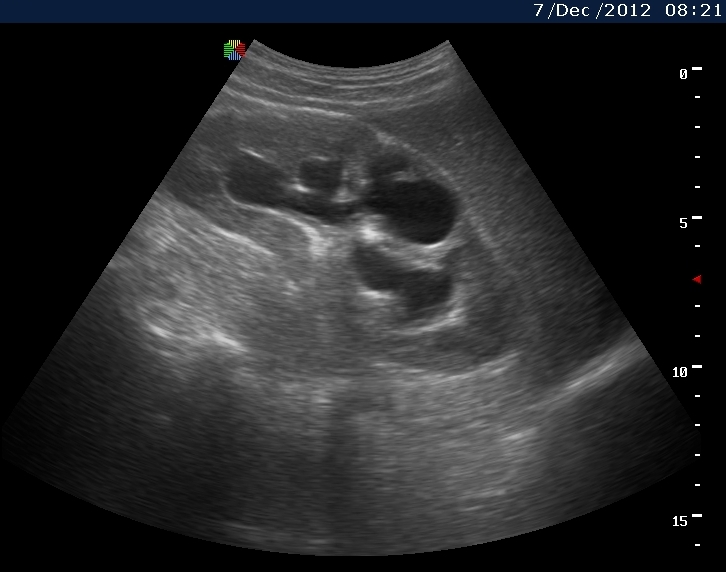

Вот как выглядит почка при первом осмотре и в феврале

1.jpg

3февраль.jpg

Видим длительно существующий гидронефроз вследствие процесса в области лоханочно-мочеточникового сегмента (видео 1), с утолщением стенок ЧЛС и истончением паренхимы почки - наиболее частая причина у взрослых - туберкулез.